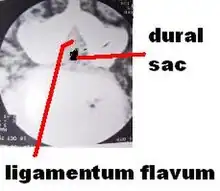

Before the advent of CT scanning, the pathology in failed back syndrome was difficult to understand. Computerized tomography in conjunction with metrizamide myelography in the late 1960s and 1970s allowed direct observation of the mechanisms involved in post operative failures. Six distinct pathologic conditions were identified:

- Spinal stenosis

Spinal stenosis

Spinal stenosis can be a late complication after laminectomy for disc herniation or when surgery was performed for the primary pathologic condition of spinal stenosis.[8][70][71] In the Maine Study, among patients with lumbar spinal stenosis completing 8- to 10-year follow-up, low back pain relief, predominant symptom improvement, and satisfaction with the current state were similar in patients initially treated surgically or nonsurgically. However, leg pain relief and greater back-related functional status continued to favor those initially receiving surgical treatment.[72]

A large study of spinal stenosis from Finland found the prognostic factors for ability to work after surgery were ability to work before surgery, age under 50 years, and no prior back surgery. The very long-term outcome (mean follow-up time of 12.4 years) was excellent-to-good in 68% of patients (59% women and 73% men). Furthermore, in the longitudinal follow-up, the result improved between 1985 and 1991. No special complications were manifested during this very long-term follow-up time. The patients with total or subtotal block in preoperative myelography achieved the best result. Furthermore, patients with block stenosis improved their result significantly in the longitudinal follow-up. The postoperative stenosis seen in computed tomography (CT) scans was observed in 65% of 90 patients, and it was severe in 23 patients (25%). However, this successful or unsuccessful surgical decompression did not correlate with patients' subjective disability, walking capacity or severity of pain. Previous back surgery had a strong worsening effect on surgical results. This effect was very clear in patients with total block in the preoperative myelography. The surgical result of a patient with previous back surgery was similar to that of a patient without previous back surgery when the time interval between the last two operations was more than 18 months.[73]

Post-operative MRI findings of stenosis are probably of limited value compared to symptoms experienced by patients. Patients' perception of improvement had a much stronger correlation with long-term surgical outcome than structural findings seen on postoperation magnetic resonance imaging. Degenerative findings had a greater effect on patients' walking capacity than stenotic findings.[74][75]

Postoperative radiologic stenosis was very common in patients operated on for lumbar spinal stenosis, but this did not correlate with clinical outcome. The clinician must be cautious when reconciling clinical symptoms and signs with postoperative computed tomography findings in patients operated on for lumbar spinal stenosis.[76]